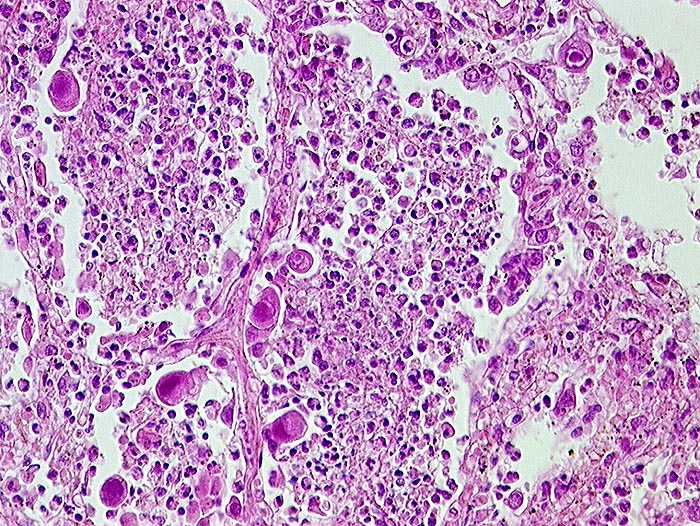

AP/ Cytomegalievirus-Infekt der Lunge

Cytomegalievirus-Infekt der Lunge

Entzündung infektiös

Lunge